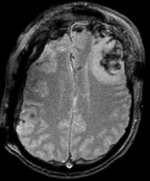

Exam 2 aligned to Exam 1 (affine only)

Exam 2 aligned to Exam 1 (affine+BSpline)

BSpline deformation only of Exam 2